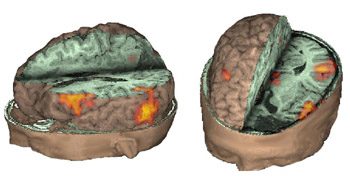

Joven diestro de 17 años de edad con epilepsia motora parcial intratable. La IRM mostró anomalía de señales en la circunvolución frontal media izquierda compatible con displasia cortical.

Representación triple: IRM (T1), IRM-FLAIR e IRMf.

Vista rostral superior izquierda

IRM de la cabeza con exposición parcial del cerebro y el cráneo. Una vista axial localizada en el tercio superior de la circunvolución frontal inferior muestra, en rojo, la activación obtenida con una tarea de generación de verbos. El punto amarillo representa la lesión y se deriva de una secuencia de recuperación de la inversión atenuada por líquido (fluid attenuated inversion recovery, FLAIR) y, presentado con el resto de las imágenes, revela la relación entre la lesión y las áreas elocuentes.